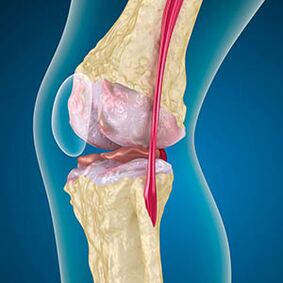

With arthrosis, the cartilage that lines the edges of the bones is abrasion or completely absent.The damaged tissue is not a source of pain, because it has no receptors.Inflammation in nearby structures causes characteristic symptoms.

The body continues the regeneration of damaged tissues, but the cartilage grows in a non -uniform way.Consequently, irregularities are formed that damage other elements of the joint.The nature of osteophytes is explained by the compensation of smooth joint cartilage.Another version indicates that the growth of "spurs"It is associated with an attempt to stabilize the medialy or lateral joint due to muscle hip.

The arthrosis of the knee joint combines two processes: the destruction of cartilage and the growth of osteophytes or bone spurs.The stadium of the process is determined by the X -ray.Arthosis is believed to be the destruction of the knee joints with age, the natural aging process.The causes are muscle weakening and poor blood supply to the fabrics.How to treat you without surgery?Delete the factors that have reduced muscle tone.